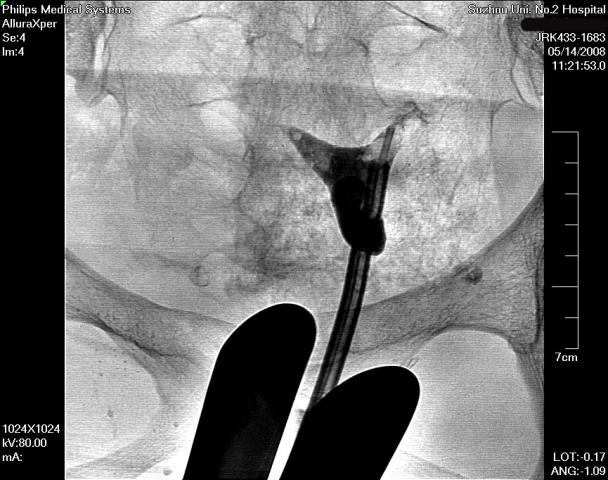

在清晰的DSA(数字减影血管造影机)的同步监测,采用同轴导管系统,进行输卵管选择性造影和再通术,主要适用于输卵管阻塞于间质部及狭部的不孕症患者,各段输卵管阻塞均可行选择性输卵管造影、通液。主要采用导管扩张术,插入导管导丝,利用导管导丝的推进扩张分离作用和造影剂的冲击力等,使输卵管疏通至伞端。手术安全高效,痛苦小,无需住院,复通率及术后妊娠率均较高。(见图1术前HSG宫腔形态正常,双侧输卵管不显影、图2左侧输卵管顺利通过导丝后造影剂通过畅、图3右侧输卵管通过导丝后畅)